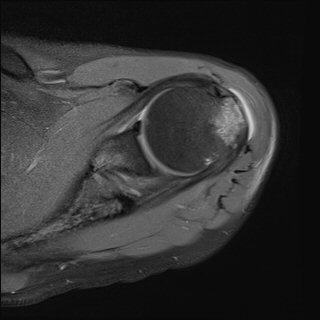

ÀÚ±â°ø¸í°Ë»ç

»ó¿Ï°ñµÎ ´ë°áÀý °ß¿­°ñÀý

mr»çÁø

2049205267_4f017b21_MR185230193.jpg